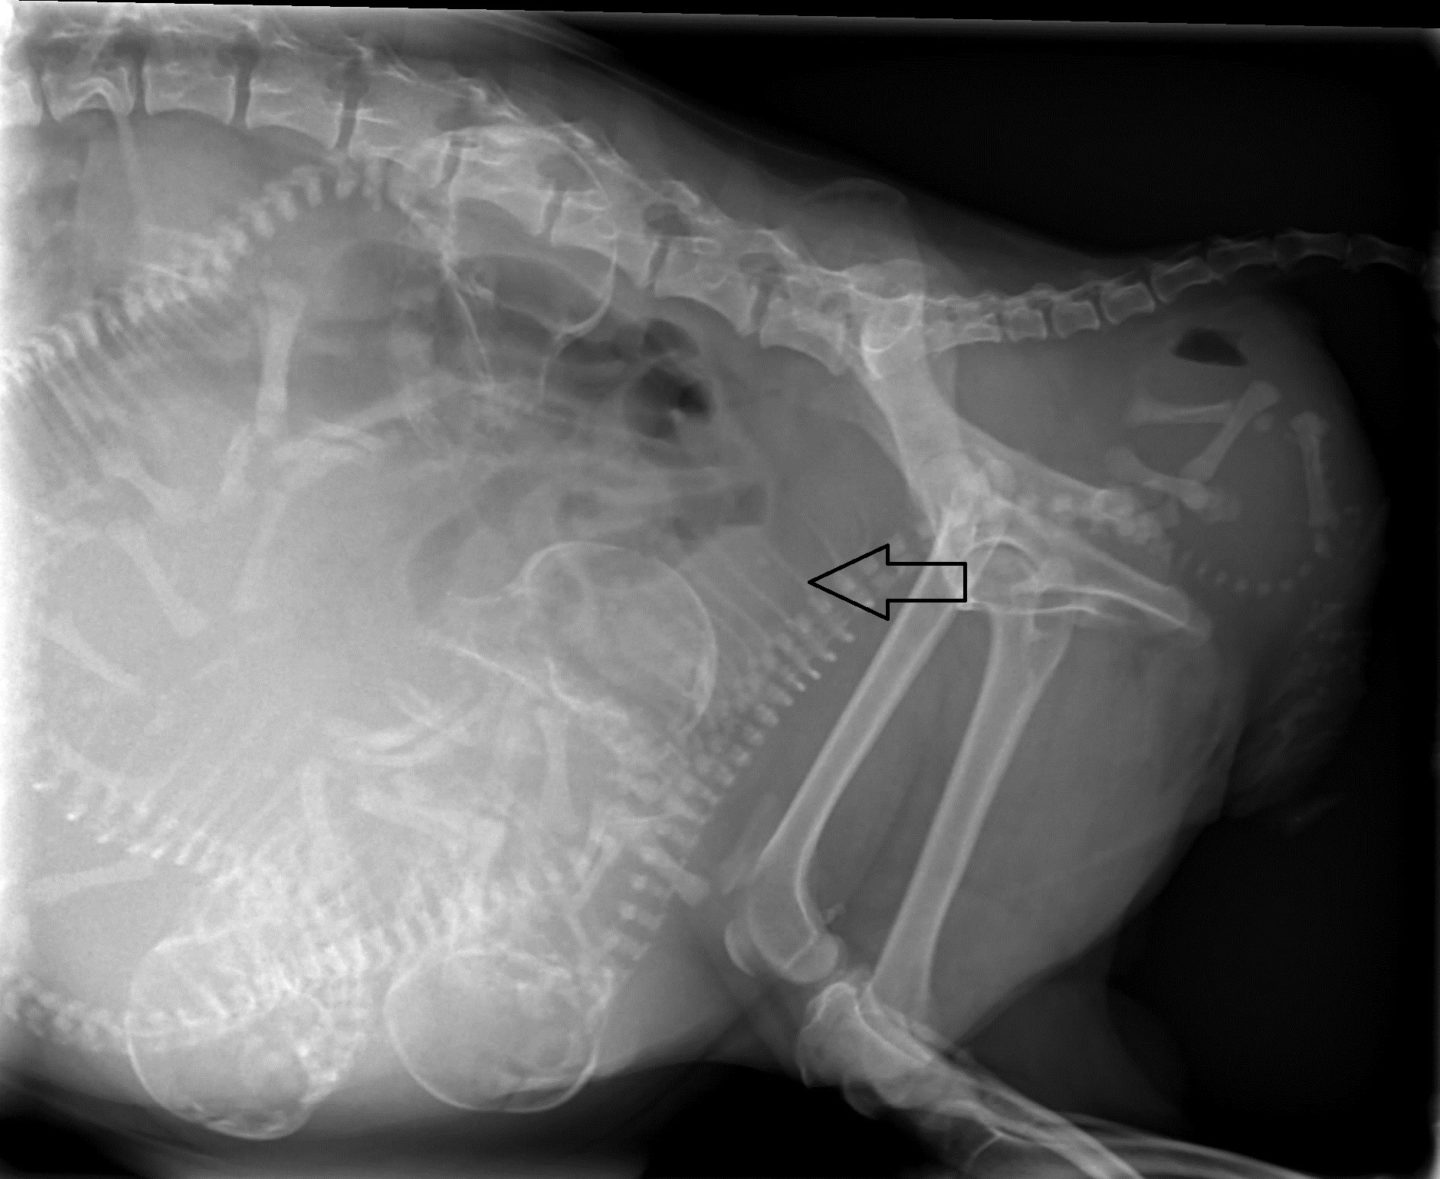

Das Röntgenbild gab den Blick auf vier normal entwickelte Welpen frei. Das Ultraschallbild bestätigte die Lebensfähigkeit aller Früchte. Die Rastlosigkeit der Mutter war damit auf glücklichste Art und Weise erklärt. Zwei Wochen später war es dann so weit. Aufgelöst rief die Besitzerin uns an und berichtete vom Abgang einigen Fruchtwassers, den Wehen der Hündin. Es erschien allerdings kein Welpe.

Letzteres ist gerade bei Chihuahuas mit ihren großen, runden Köpfen durchaus eine Möglichkeit, die einem in einem solchen Moment in den Sinn kommt. Wir entschieden uns, Bailey zu uns in die Praxis bringen zu lassen. Sie selbst war in guter Verfassung, ihre Wehen kamen kräftig in regelmäßigen Intervallen. Ein Röntgenbild brachte jedoch ans Licht, weswegen die Geburt nicht in die Gänge kommen wollte: Der erste Welpe befand sich in Hinter-Endlage auf dem Rücken liegend. An sich ist eine Geburt mit den Hinterbeinen voran beim Hund möglich, doch die Drehung des Fetus auf den Rücken verhinderte, dass sich sein Körper dem Geburtsweg seiner Mutter anpassen konnte. Er steckte fest. Von vaginal ließen sich seine Füßchen greifen und sein Körper in eine halbwegs aufgerichtete Position bringen – bei einer Mutter in der Größe eines Chihuahua kein leichtes Unterfangen – doch mit jeder Wehe drehte er sich wieder in die alte Lage zurück.